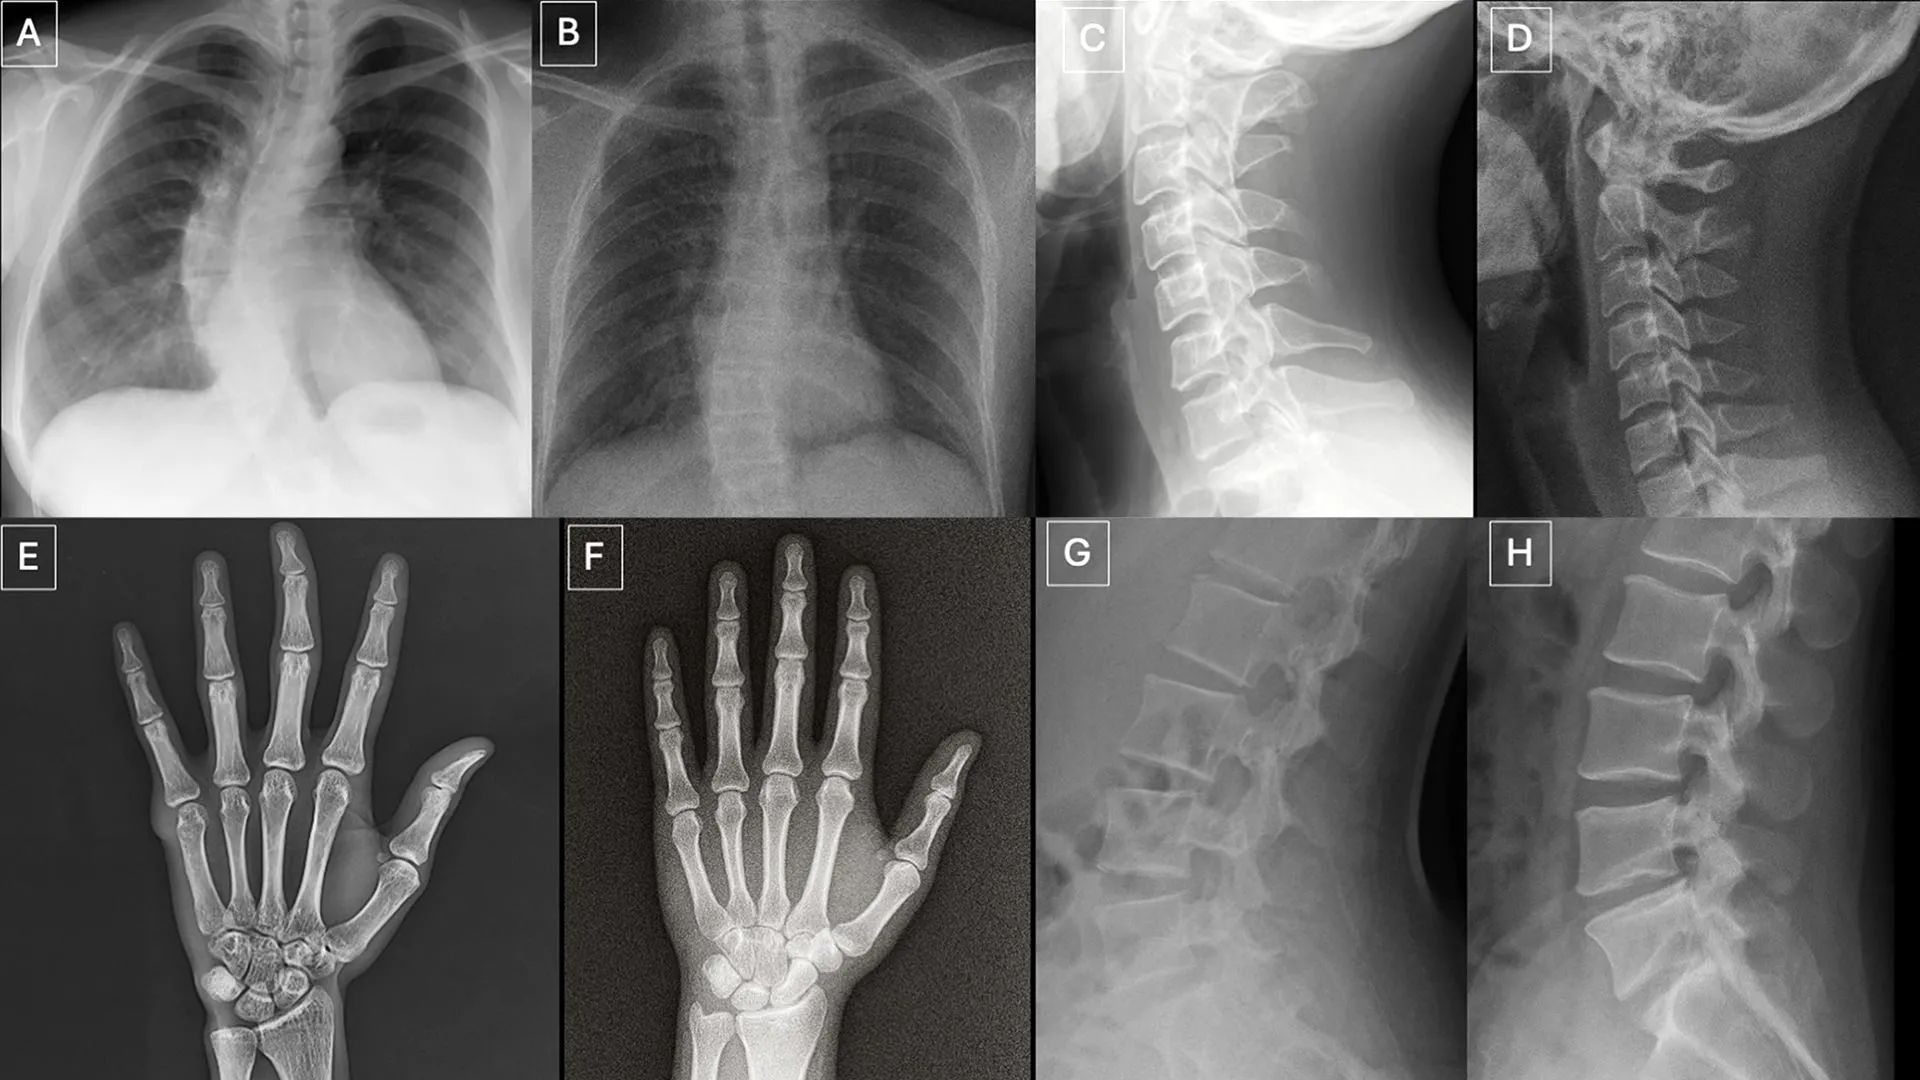

Os participantes revisaram dois conjuntos separados de imagens sem sobreposição. Um conjunto consiste em uma mistura de imagens reais e raios X gerados pelo ChatGPT de diferentes partes do corpo. O segundo conjunto concentra-se em radiografias de tórax, metade reais e metade geradas usando raios X, um modelo de difusão de IA generativo de código aberto desenvolvido por pesquisadores da Stanford Medicine.

O desempenho varia muito entre os indivíduos. Os radiologistas identificaram corretamente entre 58% e 92% das imagens geradas pelo ChatGPT. Os sistemas de IA mostraram limitações semelhantes. Quatro LLMs multimodais – GPT-4o (OpenAI), GPT-5 (OpenAI), Gemini 2.5 Pro (Google) e Llama 4 Maverick (Meta) – alcançaram taxas de precisão que variam de 57% a 85%. Mesmo o ChatGPT-4o, usado para gerar imagens deepfake, não conseguiu detectá-las, embora tenha tido um desempenho melhor que os outros modelos.

Para radiografias de tórax geradas por RoentGen, os radiologistas alcançaram taxas de precisão entre 62% e 78%, enquanto os modelos de IA variaram de 52% a 89%.

Os pesquisadores identificaram vários padrões que podem aparecer em imagens sintéticas.

“Imagens médicas deepfake muitas vezes parecem perfeitas demais”, diz o Dr. Tordzman. “Os ossos são excessivamente lisos, as espinhas são excepcionalmente retas, os pulmões são excessivamente simétricos, os padrões dos vasos sanguíneos são excessivamente uniformes e as rachaduras são excepcionalmente claras e consistentes, muitas vezes confinadas a um lado do osso”.